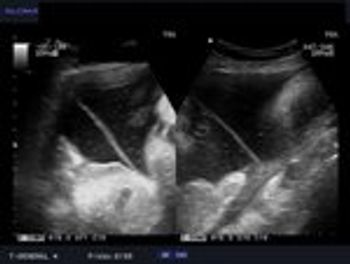

These are ultrasound images from a 2nd trimester pregnancy.